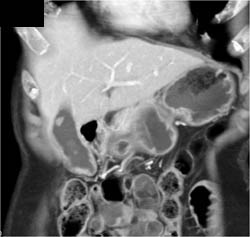

Islet Cell Tumor Growing Posteriorly